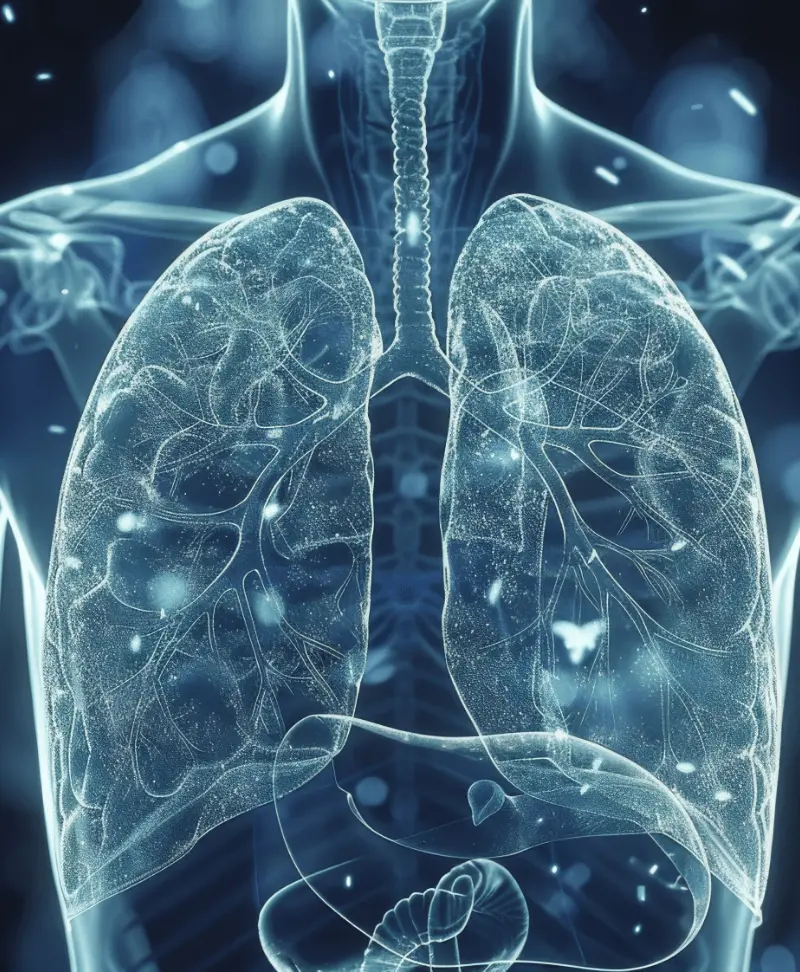

呼吸システムの構造と機能

呼吸システムは、酸素を体内に取り込み、二酸化炭素を排出する重要な役割を担っています。

呼吸の過程は、鼻腔、喉、気管、気管支、肺のシステムが連携し、酸素を肺に輸送します。

吸入した空気は、まず鼻腔で温められ、湿度が調整された後、喉を通り気管へと送られます。

気管から分岐した気管支は、さらに細かい気道に酸素を供給し、最終的に肺に達します。

肺では、酸素と二酸化炭素の交換が行われ、酸素が血液に供給され、二酸化炭素は体外に排出されます。

呼吸は自律神経によって制御され、酸素が不足すると脳が反応し、呼吸の深さや頻度を調整します。

この一連のプロセスにより、体内に必要な酸素が供給され、健康を維持するために欠かせない役割を果たしています。